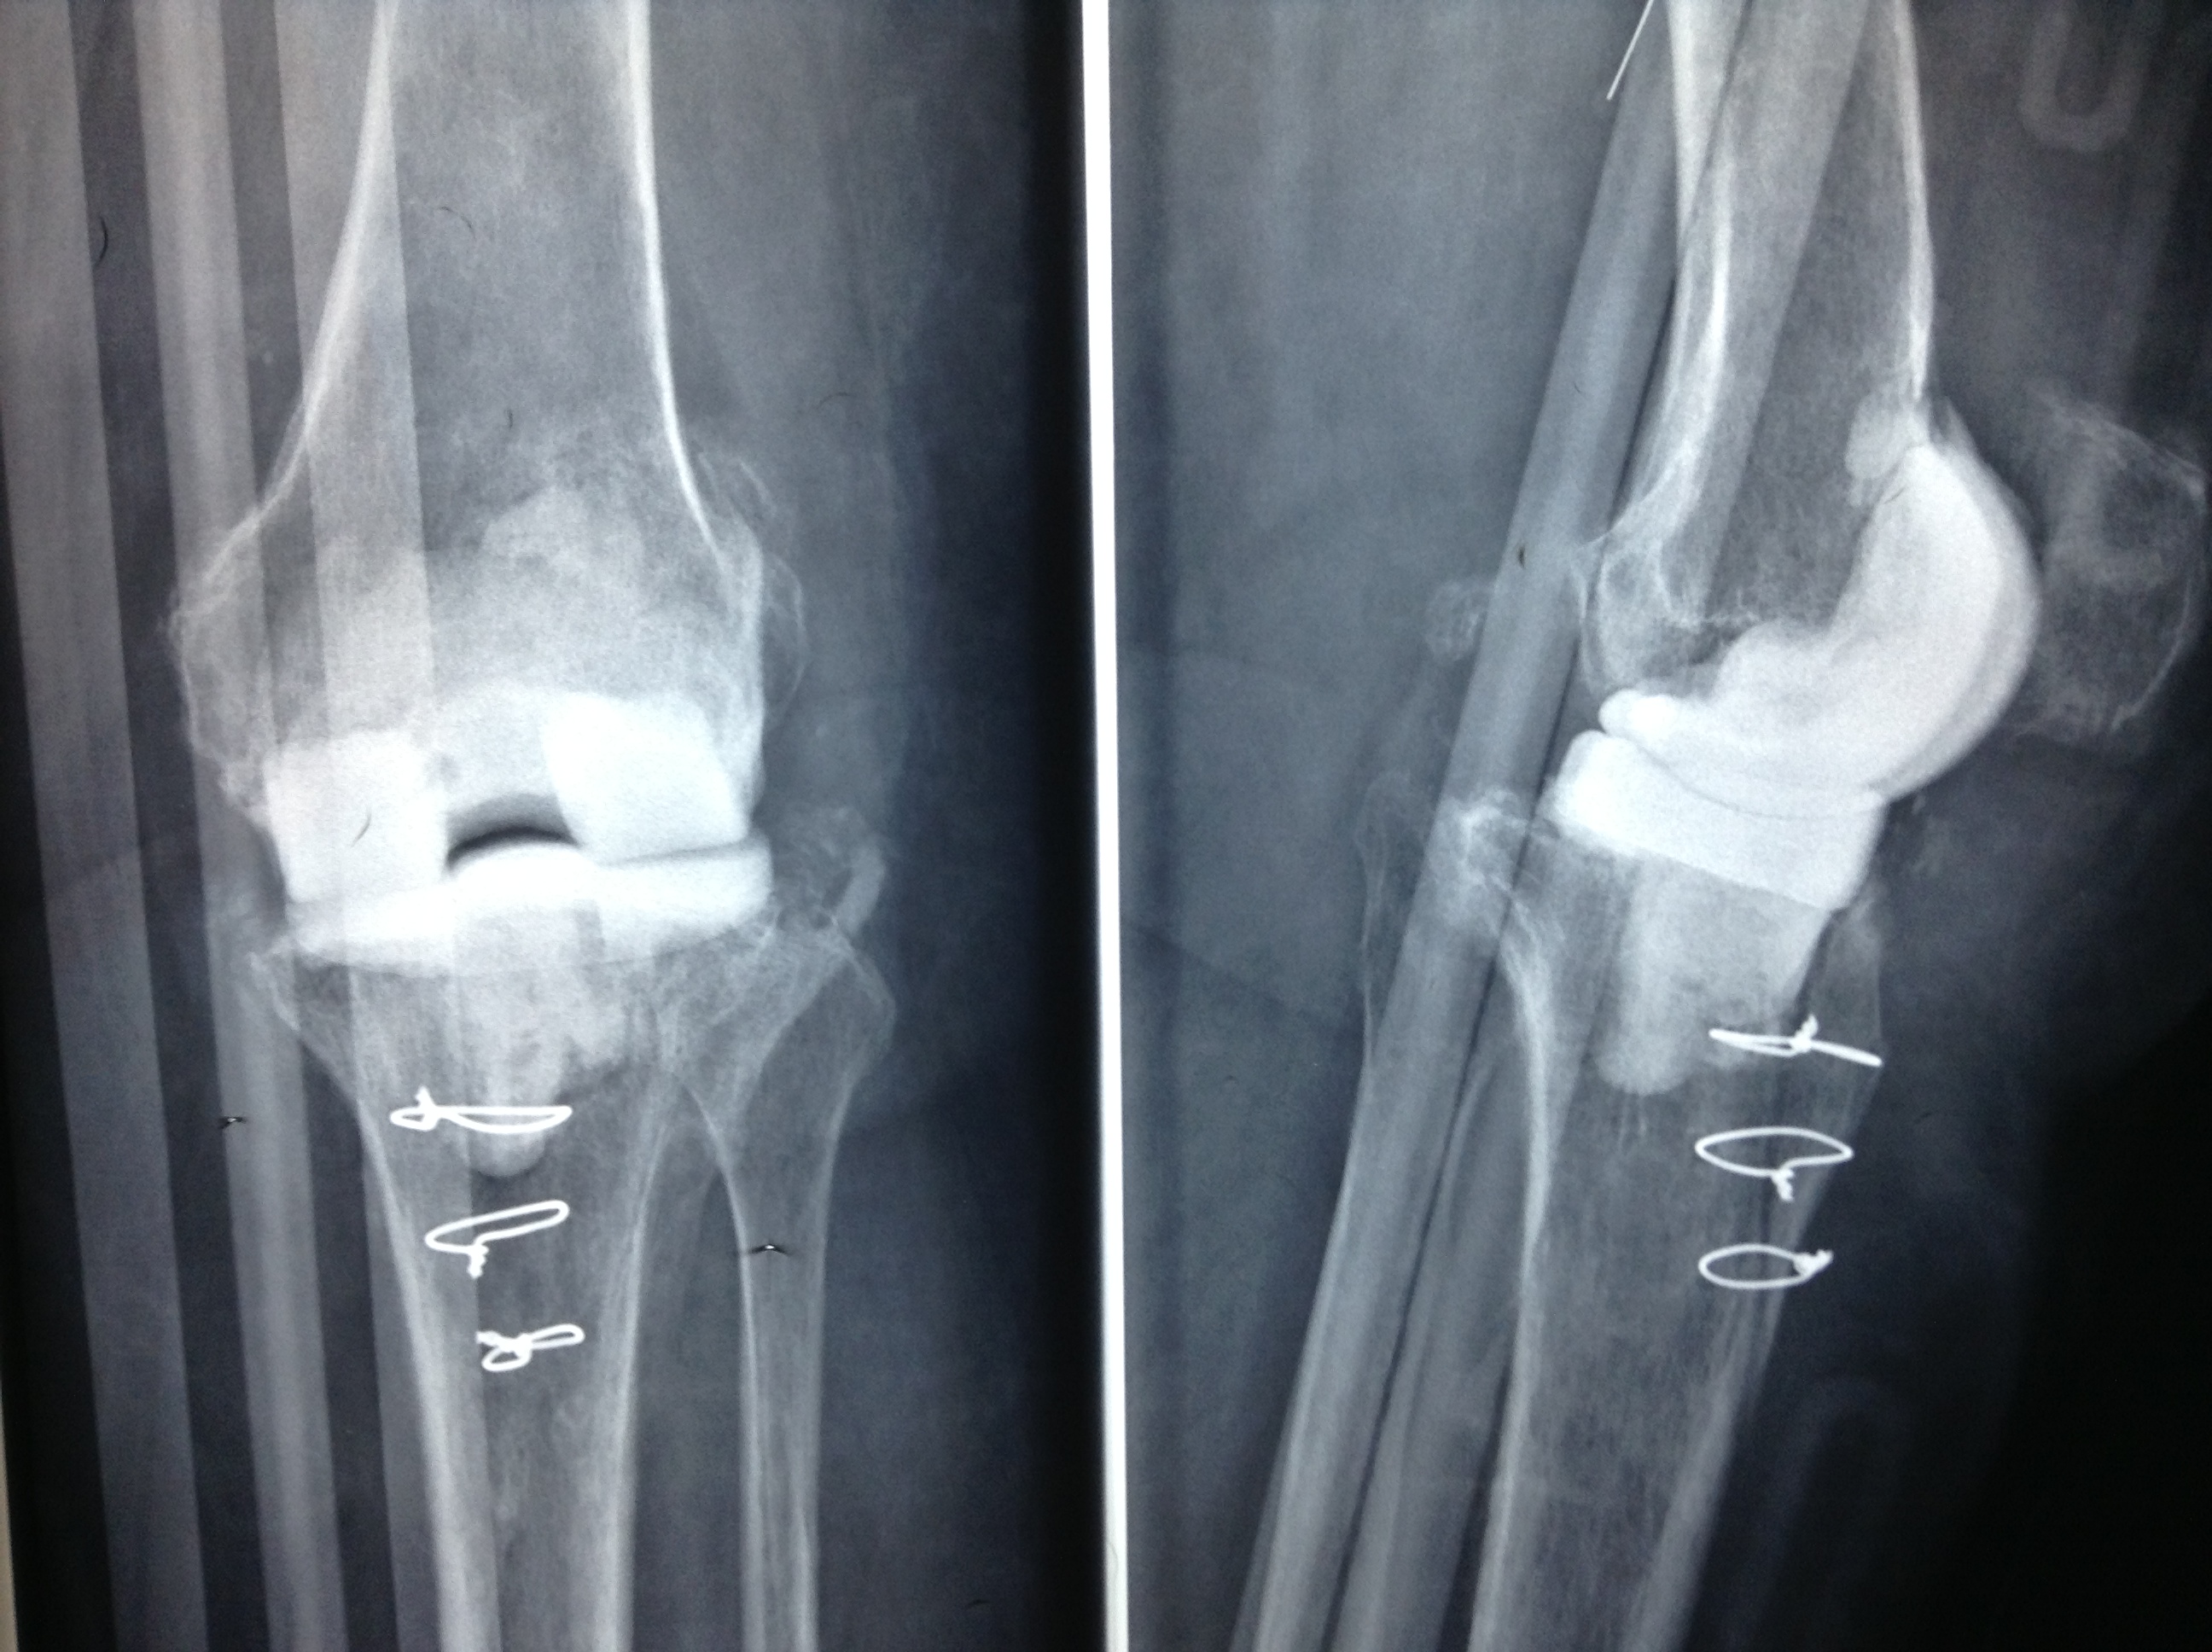

Revision Total Knee Replacement After Infection